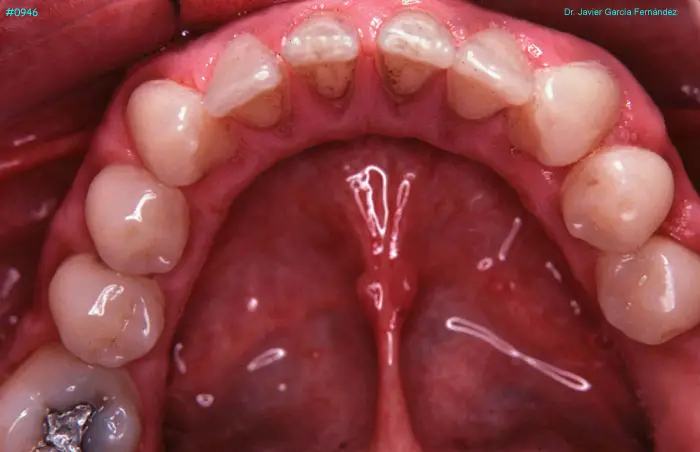

Atlas of Surgical Techniques in Periodontics. Chapter III. Atlas de Técnicas Quirúrgicas en Periodoncia